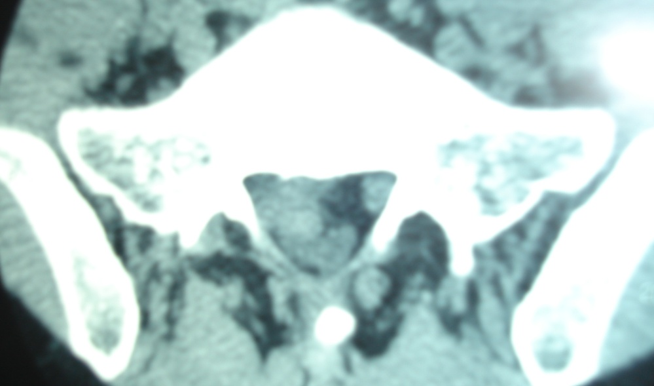

Thessys椎间孔镜优缺点THESSYS可以用于任何疝出的椎间盘微创伤手术。所有隔离的椎间盘物质和腰部脊柱的脱出(包括第5腰椎和第1骶椎间隙)都可以使用整个系统在局麻下经侧方的椎间孔摘除。整个系统的使用适用于任何由疝出的椎间盘或较大的突出引起的神经根症状或长期疼痛,保守治疗不能获得足够的改善。对于任何疝出的椎间盘的手术,THESSYS手术也需要术前彻底的磁共振,计算机断层和常规的放射线影像检查。